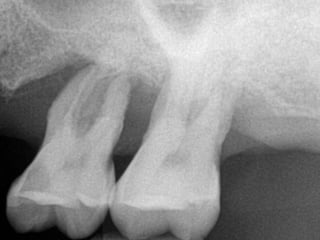

Crown Root Ratio Tooth Related

Contended

Contraindications

Referral might be

required

Extraction might

be required